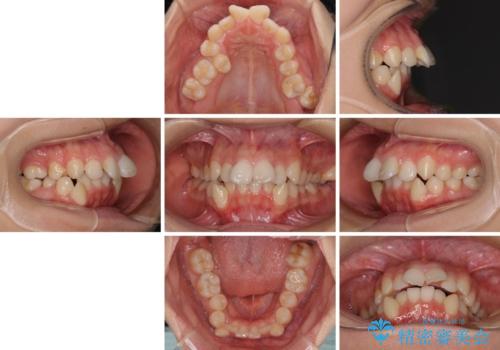

- 咬み合わせと、前歯のデコボコや八重歯、飛び出した口元を気にして来院された患者様です。

上顎は歯列不正が強く、右側臼歯部の咬み合わせは歯1本分ずれている状態でした。

補助装置を用いて奥歯の咬み合わせを改善しながら歯列を後方に移動させ、上下左右第一小臼歯を4本抜歯することで八重歯や口元の突出感を改善することとしました。

奥歯の咬み合わせの不正が顕著であったため、表側のワイヤー装置を選択して矯正治療を行うこととしました。